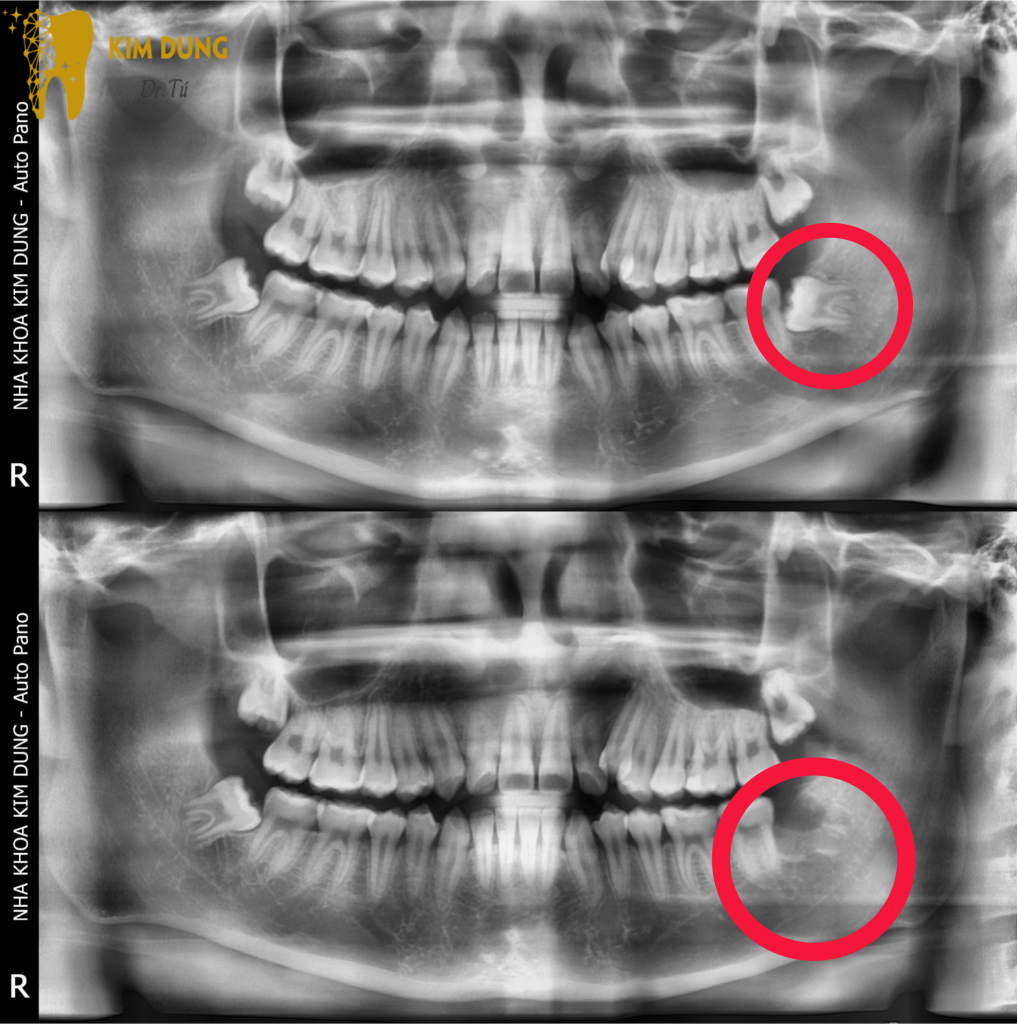

🦷Nhổ răng khôn là một 𝐪𝐮𝐚́ 𝐭𝐫𝐢̀𝐧𝐡 𝐩𝐡ẫ𝐮 𝐭𝐡𝐮ậ𝐭 𝐜𝐡𝐮𝐲𝐞̂𝐧 𝐬𝐚̂𝐮 𝐯𝐚̀ 𝐜ầ𝐧 𝐬ự 𝐜𝐡𝐮𝐲𝐞̂𝐧 𝐧𝐠𝐡𝐢ệ𝐩. Tại nha khoa 𝐊𝐢𝐦 𝐃𝐮𝐧𝐠 𝐃𝐫 𝐓𝐮́ ,chúng tôi hiểu tầm quan trọng của quá trình này và cam kết cung cấp dịch vụ nhổ răng khôn an toàn và hiệu quả.